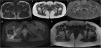

Composition of MR images on the axial plane. T1-weighted (A and B) and STIR (C) sequences. (A) Image of normal anatomy. (B) Patient number 2 in our series: bilateral decrease in the ischiofemoral space (white arrows). (C) The same patient, where there is also slight oedema in the soft tissues (femoral square) of the right ischiofemoral space and atrophy in both. D) MR image of axial plane. Proton density-enhanced (PD) sequence with fat saturation. Thickening with oedema and haematoma in the right quadratus femoris muscle (*) due to rupture in patient with ischiofemoral space impingement. (E) MRI image in axial plane. T1-weighted sequence. Measurement of the femoral square and ischiofemoral space in patient with impingement.

Magnetic resonance imaging (MRI) of the hip is the gold standard test for decreasing the ischiofemoral space (Fig. 1).12 Impingement is considered when the ischiofemoral space is less than 23 (±8) cm, or when the width of the quadratus femoris muscle is less than 12 (±4) cm.5,8 However, there is controversy with the use of these reference values,1,11 given that this space is highly variable depending on the gait cycle and the patient's position during the imaging test, and MRI tends to overestimate its measurement, so the physical examination of the patient is essential in the diagnosis of this pathology. MRI can also detect alteration of the quadratus femoris muscle signal due to oedema or fibre rupture, fat infiltration in cases of chronic impingement, or insertional tendinopathy of the hamstrings or iliopsoas.2,9,11 Another technique that is very useful is dynamic hip ultrasound to corroborate the impingement of the ischiofemoral space with the change in position of the lower limb, as well as to assess whether the patient's symptoms are due to impingement or other causes.11